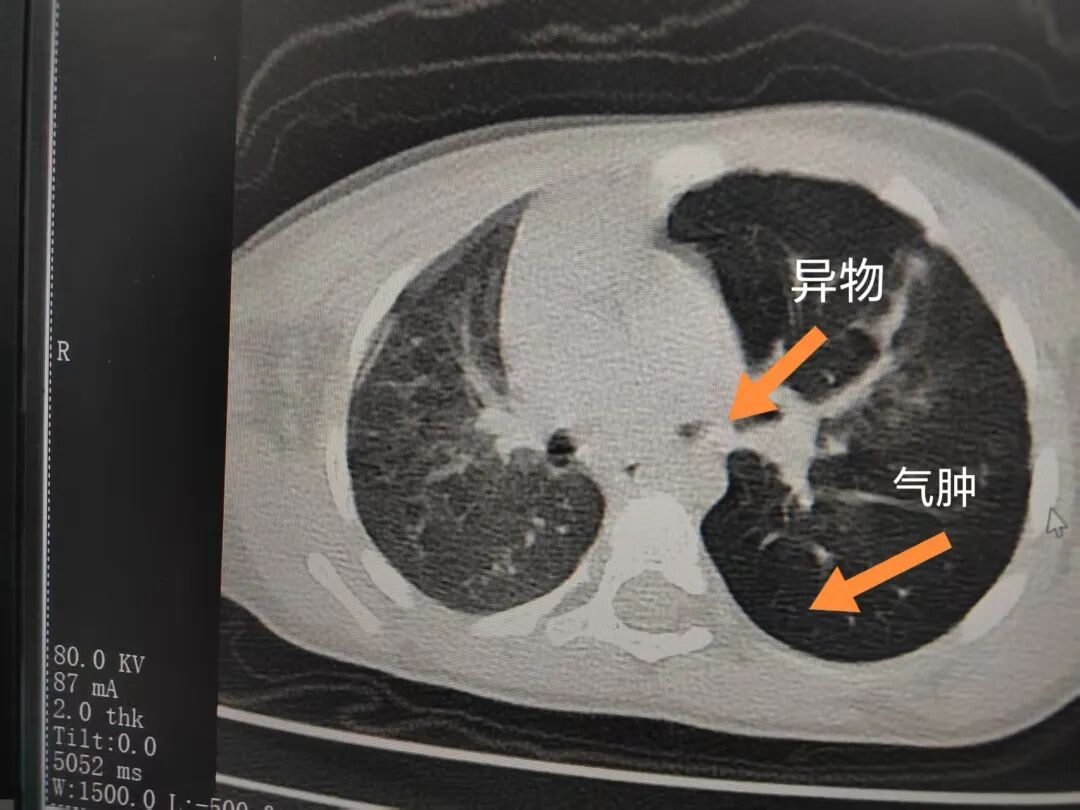

三天后(11月13日),趙寶出現(xiàn)高熱、咳喘加重,家長著急了,再次帶他來到醫(yī)院。CT檢查顯示左肺過度充氣,左肺上下葉支氣管主干見不規(guī)則高密度影,左肺上葉可見大片狀密度增高影,縱隔窗實變,提示為“左側(cè)支氣管內(nèi)異物并繼發(fā)性改變,左肺上葉舌段肺膨脹不全”。

市二院小兒呼吸內(nèi)科副主任楊亞娟介紹,異物誤入氣道可能導致氣道阻塞,嚴重時可引發(fā)窒息,甚至危及生命。若異物進入支氣管,造成不完全堵塞,可引起阻塞性肺氣腫;如完全堵塞支氣管,則可能導致肺組織萎縮,形成肺不張。此外,若異物存留時間較長,或為植物性異物,容易合并細菌感染,產(chǎn)生膿性分泌物,進而發(fā)展為肺炎。她強調(diào),盡早診斷并取出異物,是減少并發(fā)癥、降低病死率的關鍵。